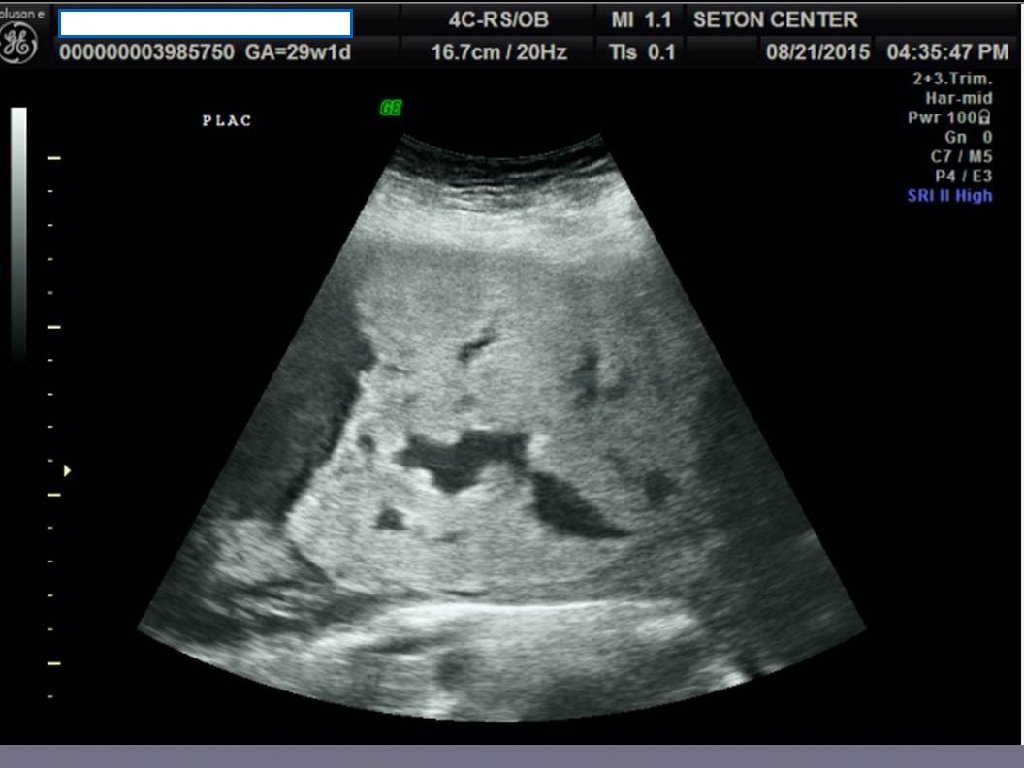

Prenatal Diagnosis • When the diagnosis is made it is usually made by ultrasound in the second or third trimester. • Sonographic findings suggestive are • • loss of normal hypoechoic retroplacental zone • multiple vascular lacunae (irregular vascular spaces) within the placenta “swiss cheese” appearance • blood vessels or placental tissue bridging the uterine-placental margin, myometrialbladder interface, or crossing uterine serosa • retroplacental myometrial thickness < 1 mm • numerous coherent vessels visualized with 3 -D color/power Doppler in a basal view. If sonographic findings are inconclusive or a placenta percreta is suspected, MRI may be useful.

Ultrasound Findings Suggesting Morbidly Adherent Placenta First trimester • • Gestational sac that is located in the lower uterine segment • Multiple irregular vascular spaces noted within the placental bed • Implantation of gestational sac imbedded into cesarean delivery sac (“cesarean scar ectopic”) Second trimester • • Multiple vascular lacunae within placenta

Ultrasound Findings Suggesting Morbidly Adherent Placenta • Third trimester • Loss of normal hypoechoic retroplacental zone • Presence of multiple vascular lacunae within placenta (Swiss-cheese appearance) • Abnormalities of uterine serosa-bladder interface (intertuption of line, thickening of line, irregularity of line, and increased vascularity • Extension of villi into myometrium, series, or bladder • Retro-placental myometrial thickness of< 1 mm • Turbulent blood flow through lacunae on Doppler ultrasonography • Increased subplacental vascularity • Vessels bridging form placenta to uterine margin • Gaps in myometrial blood flow